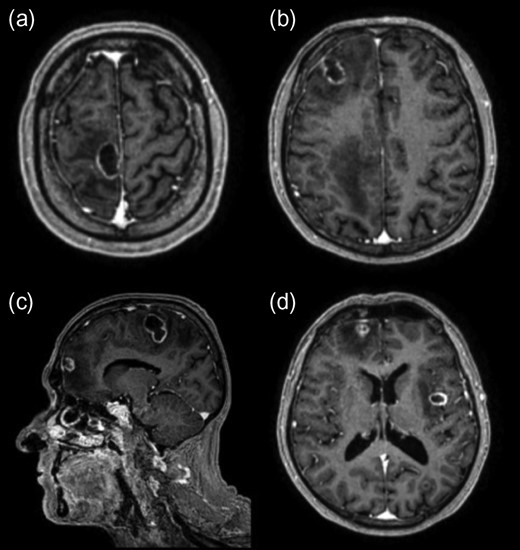

Commencement of dexamethasone (8 mg twice-daily) initially resulted in a good clinical response. Image-guided excision of the right frontal abscess was undertaken and culture results identified Nocardia farcinica. Despite appropriate treatment with intravenous linezolid combined with imipenem and the subsequent addition of co-trimoxazole, repeat imaging demonstrated a continued increase in size of the remaining abscesses. Two further operations were performed over a 4-week period in addition to ongoing anti-microbial therapy. Resection of all abscesses was achieved through right frontal, right parietal, left parieto-occipital and left temporal craniotomies. Microbiological analysis identified Enterococcus faecium in a second abscess and vancomycin was added to the antibiotic regimen. Post-operative imaging indicated complete resection and appearances were monitored with regular imaging (Fig. 2). A prolonged course of dexamethasone was required to maintain neurological function. This may have contributed to a wound dehiscence requiring an uneventful wash-out and repeat closure in theatre. Ongoing seizure activity was controlled with anticonvulsants.

Post-contrast axial T1-weighted MRI following resection of abscesses in the right frontal lobe (a, b), left insular region (b) and left occipital lobe (b).